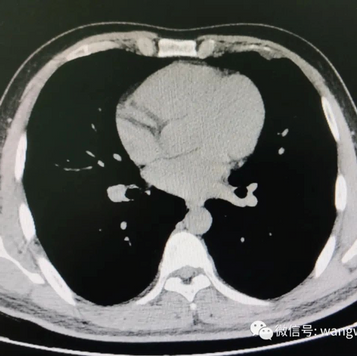

The anterior chest wall exhibits an overall protrusion, and the thoracic cage appears barrel-shaped. The patient was diagnosed with barrel chest.

CT scan before the surgery